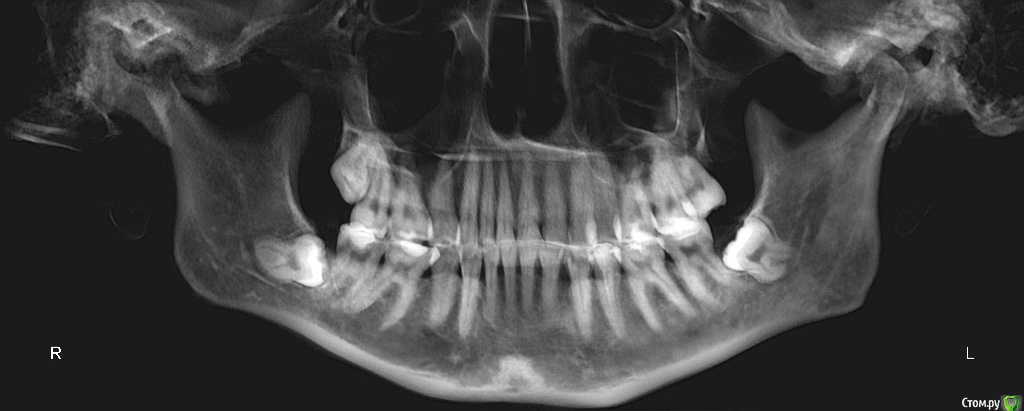

Dosya Опубликовано 12 апреля, 2018 Поделиться Опубликовано 12 апреля, 2018 Здравствуйте,в 1992 г - удалены две четверки сверху, носила пластинки около года. На нижней челюсти лечение не проводилось.в 2011 - 2012 году были удалены 2 четверки снизу, проведено ортодонтическое лечение: брекеты стояли только на нижней челюсти. В результате сформирован глубокий прикус, появилась рецессия десны на передних нижних зубах, стачиваемость зубов, дефект речи.В 2016 году обратилась к ортодонту с просьбой исправить прикус, чтобы иметь возможность нормально разговаривать. Доктор перенаправила меня к ортопедам для коррекции височно-челюстного сустава с помощью капы. Капу одеваю на ночь уже 2 года. Обещанного выдвижения челюсти и коррекции речи не произошло. Обратилась к ортодонтам повторно. Выбрала 4 ортодонтов по отзывам и получила 4 разных мнения:1. ничего не трогать, иначе, будет хуже.2. хирургическая коррекция - выдвижение нижней челюсти3. коррекция коронками высоты зубов (что не решает мою проблему с речью)и 1 доктор, все-таки, готов исправлять мой прикус брекетами Insignia после пластики десны.Мой вопрос: не выпадут ли передние нижние резцы при установке брекетов из-за недостатка костной ткани на нижней передней десне? Возможно ли в моем случае лечение без оперативного вмешательства? Ссылка на комментарий

Dosya Опубликовано 12 апреля, 2018 Автор Поделиться Опубликовано 12 апреля, 2018 Спасибо за ссылку. КТ загружены в предыдущем сообщении. Фото прилагаю. 1 Ссылка на комментарий

Monkey Опубликовано 20 апреля, 2018 Поделиться Опубликовано 20 апреля, 2018 Здравствуйте,в 1992 г - удалены две четверки сверху, носила пластинки около года. На нижней челюсти лечение не проводилось.в 2011 - 2012 году были удалены 2 четверки снизу, проведено ортодонтическое лечение: брекеты стояли только на нижней челюсти. В результате сформирован глубокий прикус, появилась рецессия десны на передних нижних зубах, стачиваемость зубов, дефект речи.В 2016 году обратилась к ортодонту с просьбой исправить прикус, чтобы иметь возможность нормально разговаривать. Доктор перенаправила меня к ортопедам для коррекции височно-челюстного сустава с помощью капы. Капу одеваю на ночь уже 2 года. Обещанного выдвижения челюсти и коррекции речи не произошло. Обратилась к ортодонтам повторно. Выбрала 4 ортодонтов по отзывам и получила 4 разных мнения:1. ничего не трогать, иначе, будет хуже.2. хирургическая коррекция - выдвижение нижней челюсти3. коррекция коронками высоты зубов (что не решает мою проблему с речью)и 1 доктор, все-таки, готов исправлять мой прикус брекетами Insignia после пластики десны.Мой вопрос: не выпадут ли передние нижние резцы при установке брекетов из-за недостатка костной ткани на нижней передней десне? Возможно ли в моем случае лечение без оперативного вмешательства? Нужно проводить полное обследование, вполне возможно, что именно ортодонтическое лечение поможет Вам сохранить нижние резцы, поскольку рецессии возникли в результате перегрузки данных зубов. Чтобы эту перегрузку устранить скорее всего потребуется повторная ортодонтия. На счет закрытия рецессий, это вам необходимо ДО ОРТОДОНТИИ проконсультироваться с пародонтологом (обозначив, что планируете ортодонтическое лечение - в идеале, если ортодонт и пародонтолог буду в одной клинике) и решить будут ли рецессии закрываться до предстоящего ортодонтического лечения, либо после. Ссылка на комментарий